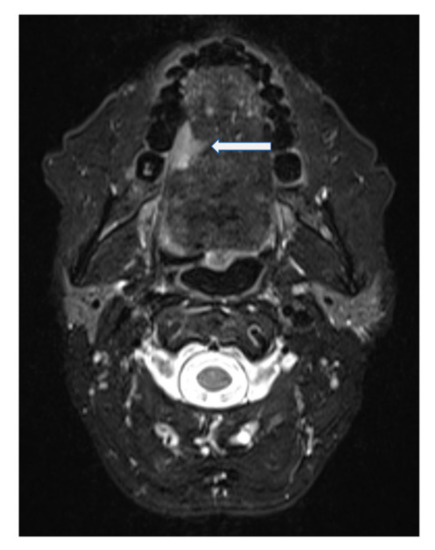

Figure 3.

T2-weighted fat-suppressed, contrast-enhanced MRI of Case 2 in the axial plane. Squamous cell carcinoma indicated by arrow.